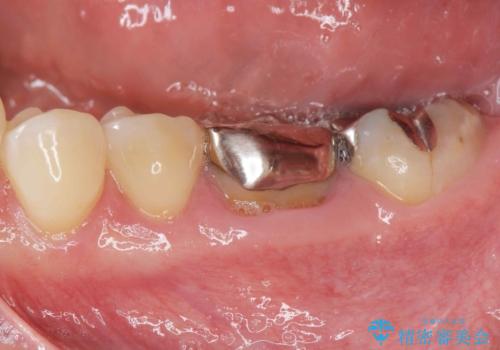

右の奥歯を機能回復|再根管治療とインプラントでしっかり噛める歯へ